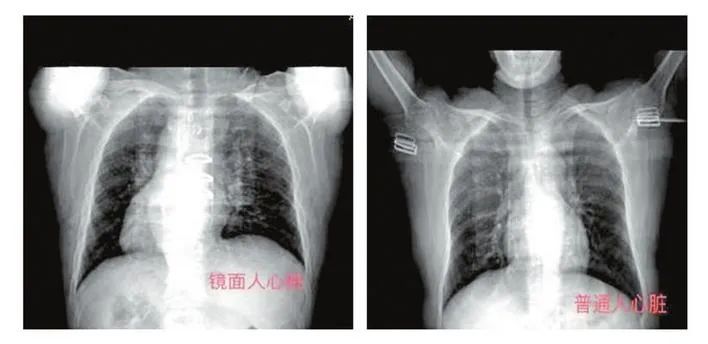

“镜面人”又称“镜子人”或“镜像人”,医学术语是“完全性内脏反位”,心脏、肝脏、脾脏、胆等器官位置均与常人相反,如同镜中影像,是人体胚胎发育过程中的突变所致,出现几率仅为百万分之一。

记者从他的CT片中也看到,以脊椎为中轴,其心脏明显偏右。近日,他进行了二尖瓣成形修复术,手术过程4小时,全程顺利。